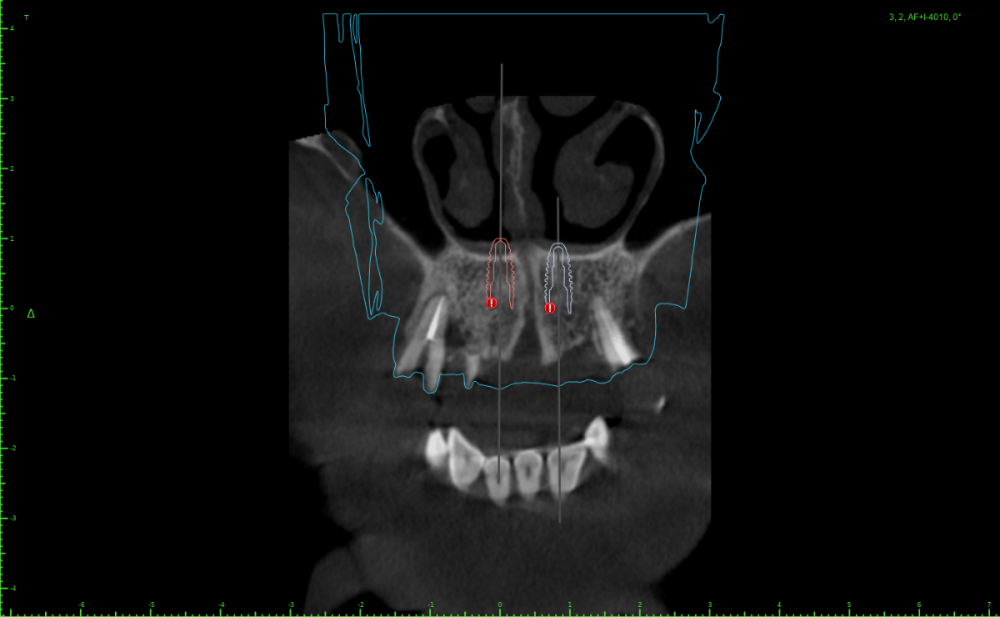

Женька Опубликовано 13 апреля, 2023 Автор Поделиться Опубликовано 13 апреля, 2023 @Irouil если я Вас правильно понял. Ссылка на комментарий

Irouil Опубликовано 13 апреля, 2023 Поделиться Опубликовано 13 апреля, 2023 @Женька да, все верно. какова длина винтов? Ссылка на комментарий

Женька Опубликовано 13 апреля, 2023 Автор Поделиться Опубликовано 13 апреля, 2023 @Irouil десятки Ссылка на комментарий

Irouil Опубликовано 13 апреля, 2023 Поделиться Опубликовано 13 апреля, 2023 В общем, я бы поставил во фронт 8-ки по дно носовой полости, боковые классически под углом не обращая внимания на дырку, ориентация сверления боковых лож небно-вестибулярная, чтобы платформа была впритык к небной стенке (даже если будет немного над ней зиять - не страшно), наскреб бы с миру по нитке авто (можно ещё редукцию провести не спиливанием, а сепарированием, тогда полученный блок можно размолоть - графта будет дофига, какой-то фрагмент покрупнее можно использовать каркасно, вклинив его между краями дефекта и мультом), плотно утрамбовал бы вокруг импланта в дефект, с неба vip-ct вокруг мульта по принципу пончо, плотно авто под лоскут Если пару винтов взять для фиксации фрагментов и их вкрутить в стенки дефекта вестибулярно от импланта, то получится вообще отличное место для вклинивания фрагмента Ссылка на комментарий

Irouil Опубликовано 13 апреля, 2023 Поделиться Опубликовано 13 апреля, 2023 @Женька почему некуда? Попробуйте расставить винты по этой схеме (фронтальные можно немного ангулировать медиально, кстати, чтобы увести их подальше от боковых), что я описал выше. Идея выставлять импланты на разные уровни мне принципиально не нравится Ссылка на комментарий